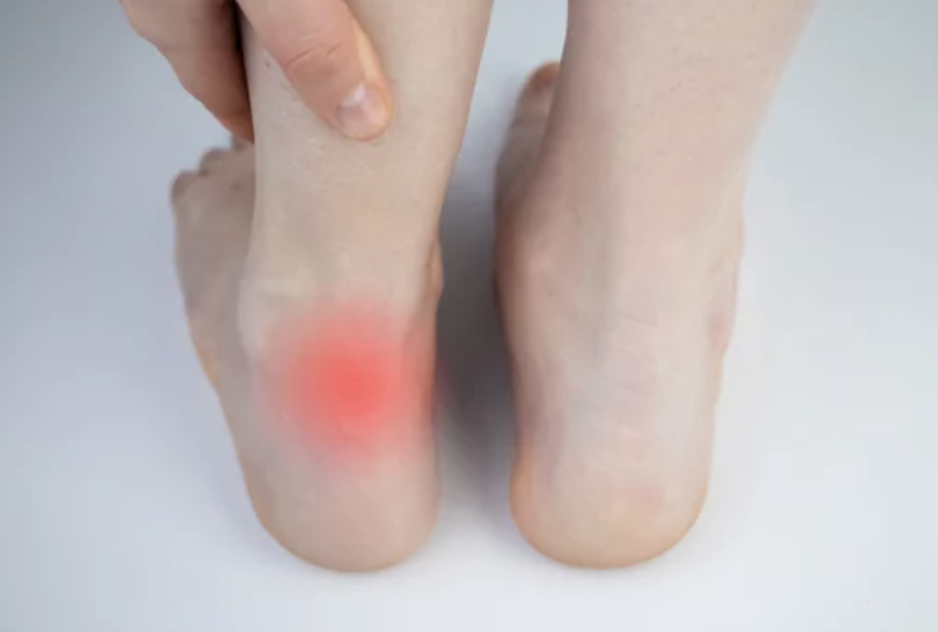

복숭아뼈 주위가 붓는 것은 많은 사람들이 겪는 일상적인 문제 중 하나입니다. 이런 증상은 종종 불편함을 초래하고 예민한 피부로 인해 자신감을 상실시킬 수 있습니다. 오늘은 복숭아뼈 주위가 붓는 이유와 해결책에 대해 자세히 살펴보겠습니다.

복숭아뼈 주위가 붓는 이유

복숭아뼈 주위 부종 해결책

복숭아뼈 주위 부종은 다양한 이유로 발생할 수 있지만, 적절한 대처와 건강한 생활 습관을 유지하면 효과적으로 관리할 수 있습니다. 위에서 소개한 해결책을 통해 불편함을 줄이고 건강한 피부를 유지하세요.